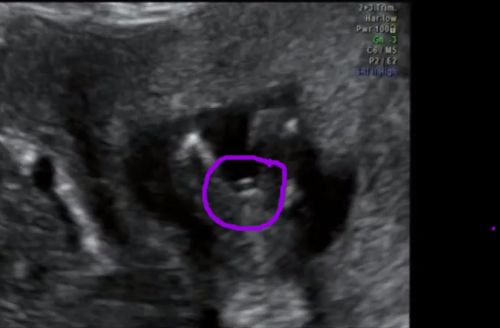

I am 6w3d and already have 2 beautiful boys :) I ordered a clairvoyant reading from etsy and was told I am having another boy :(